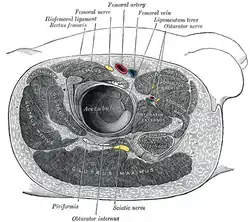

In humans, the sciatic nerve is formed from the L4 to S3 segments of the sacral plexus, a collection of nerve fibres that emerge from the sacral part of the spinal cord. The lumbosacral trunk from the L4 and L5 roots descends between the sacral promontory and ala and the S1 to S3 roots emerge from the ventral sacral foramina. These nerve roots unite to form a single nerve in front of the piriformis muscle. The nerve passes beneath piriformis and through the greater sciatic foramen, exiting the pelvis.[1]: 422–4 From here, it travels down the posterior thigh to the popliteal fossa. The nerve travels in the posterior compartment of the thigh behind (superficial to) the adductor magnus muscle, and is itself in front of (deep to) the long head of the biceps femoris muscle. At the popliteal fossa, the nerve divides into its two branches:[1]: 532

Sciatic nerve. Structures surrounding left hip-joint.